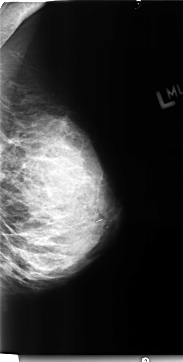

B_3127_1.RIGHT_CC

RIGHT_CC LINES 4720 PIXELS_PER_LINE 2304 BITS_PER_PIXEL 12 RESOLUTION 50 OVERLAY

FILE: B_3127_1.RIGHT_CC.OVERLAY

TOTAL_ABNORMALITIES 1

ABNORMALITY 1

LESION_TYPE CALCIFICATION TYPE PLEOMORPHIC DISTRIBUTION CLUSTERED

ASSESSMENT 4

SUBTLETY 3

PATHOLOGY BENIGN

TOTAL_OUTLINES 1

BOUNDARY